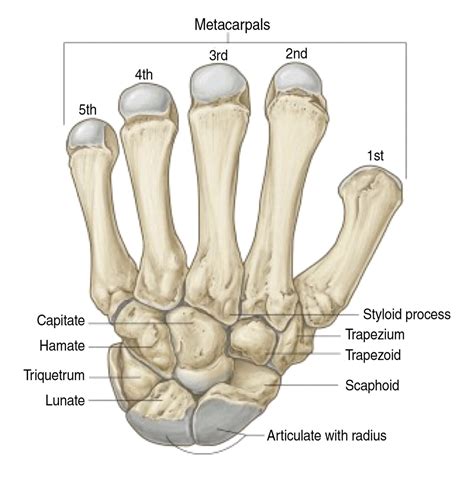

Injuries to the wrist can be debilitating, and one of the most common yet often overlooked injuries is a broken scaphoid bone. The scaphoid bone is one of the eight carpal bones in the wrist and plays a crucial role in the stability and movement of the hand. Understanding the causes, symptoms, diagnosis, and treatment of a broken scaphoid bone is essential for anyone who has experienced a wrist injury or is at risk of one.

Understanding the Scaphoid Bone

The scaphoid bone is located on the thumb side of the wrist, just below the radius bone in the forearm. It is a small, boat-shaped bone that connects the two rows of carpal bones. The scaphoid bone is particularly vulnerable to fractures due to its position and the forces it absorbs during a fall or impact.